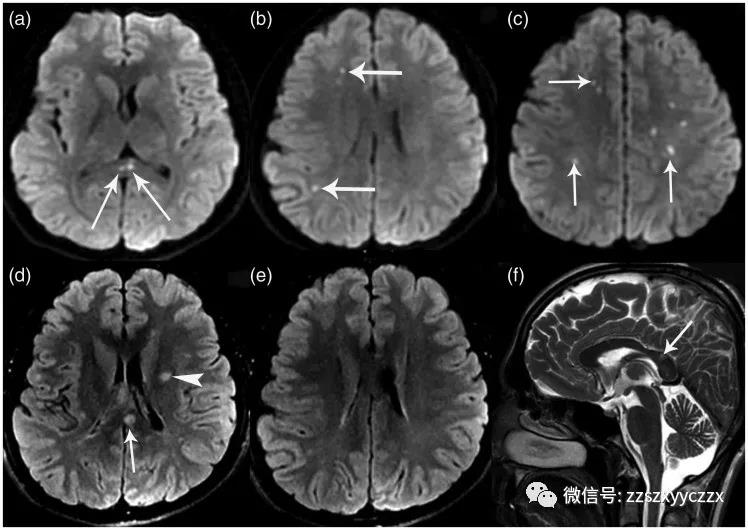

图1 初始脑部磁共振成像。(a-c)轴位DWI显示在胼胝体体压部((a)中的箭头)和脑室周围白质((b)和(c)中的箭头)中有多个弥散受限的小病灶。(d)FLAIR序列上看到左侧放射冠高信号(箭头)和胼胝体(箭头)中的高信号病变。(e)轴位FLAIR图像通过胼胝体水平上没有看到病变。(f)通过中线矢状位T2序列除了压部病变(箭头)之外,其余胼胝体显示正常。

图2 复查脑磁共振成像。(a-c)轴位DWI显示多发弥散受限区域扩大,脑室周围白质和胼胝体可见新发病灶。轴位FLAIR序列通过胼胝体(d,e)水平和矢状T2像通过中线(f)显示雪球样病变(箭头),其在胼胝体中心位置使其成为Susac’s 综合征的病理特征。